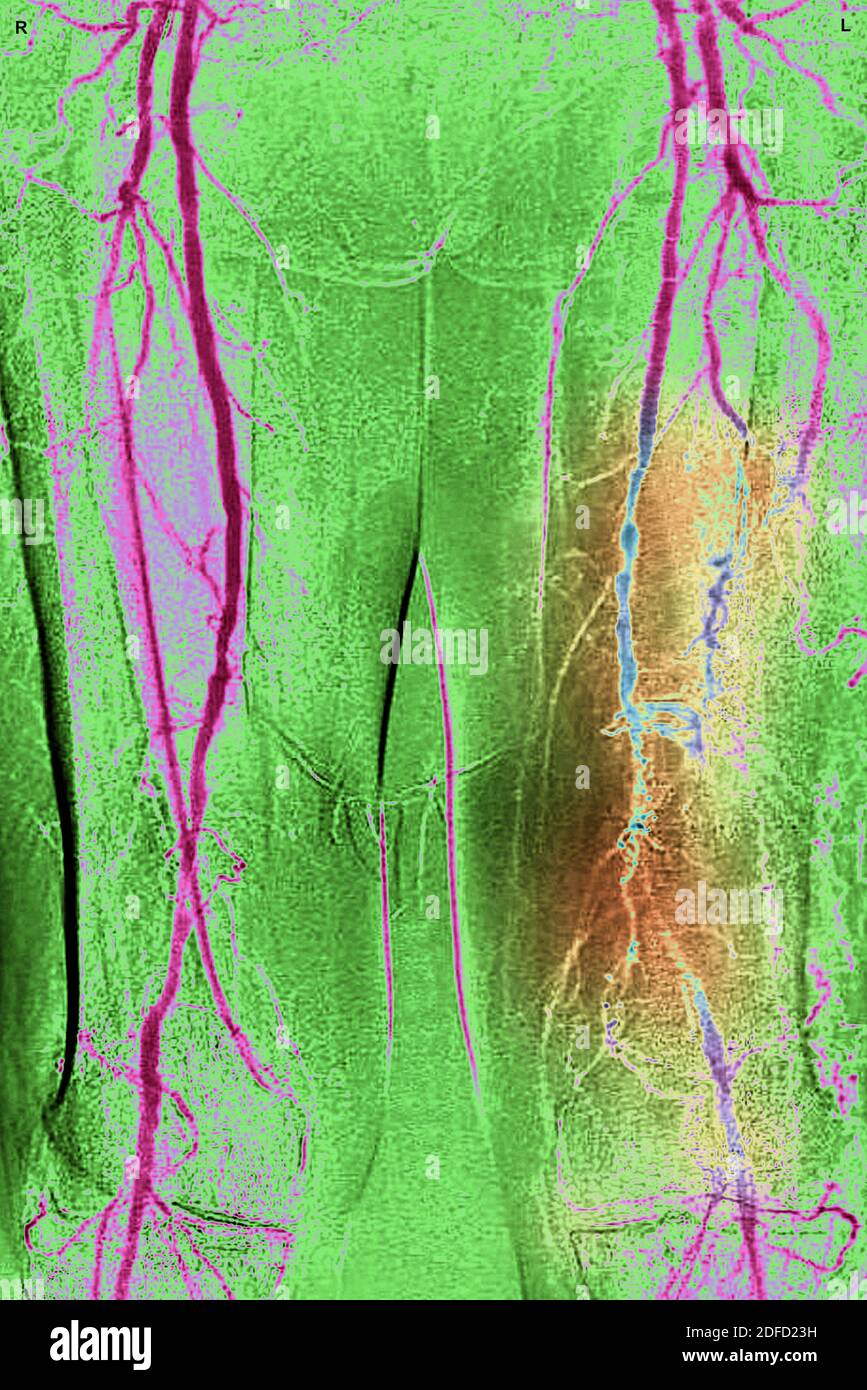

Obliterating arterial disease of the lower limbs Stock Photohttps://www.alamy.com/image-license-details/?v=1https://www.alamy.com/obliterating-arterial-disease-of-the-lower-limbs-image388134981.html

Obliterating arterial disease of the lower limbs Stock Photohttps://www.alamy.com/image-license-details/?v=1https://www.alamy.com/obliterating-arterial-disease-of-the-lower-limbs-image388134981.htmlRM2DFD23H–Obliterating arterial disease of the lower limbs